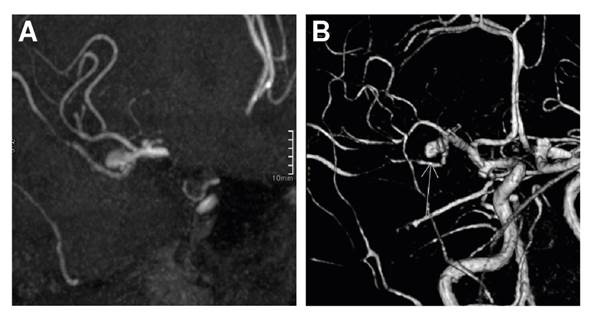

Asimismo, la paciente fue valorada por oftalmología y, en la valoración del fondo de ojo, se encontraron signos de neuropatía óptica isquémica anterior no arterítica y oclusión de la rama de la arteria retinal temporal superior en el ojo izquierdo. Ante los hallazgos de compromiso vascular, se practicó una angiorresonancia magnética en la que se observaron aneurismas saculares de múltiples territorios vasculares: en la arteria cerebral media derecha, la carótida interna y el segmento comunicante de la arteria carótida interna derecha (figura 2).

Es destacable la presencia de aneurismas en la angiorresonancia cerebral de la paciente. Aunque no fue posible comprobarlo, en el estudio histopatológico podrían corresponder a verdaderos aneurismas micóticos. Los aneurismas micóticos representan el 5 % de los aneurismas cerebrales y se han asociado al diagnóstico de diabetes mellitus 27. La etiología fúngica en los mismos es infrecuente; se han reportado casos de infección por Aspergillus spp., Candida spp. y zigomicetos, siendo Aspergillus spp. el hongo más común ya que, al producir invasión vascular, las hifas pueden generar trombosis y daño endotelial 28. El manejo quirúrgico se indica en pacientes con efecto de masa y ruptura; para los demás casos, la elección de tratamiento endovascular depende de la localización y el tamaño de las lesiones 29.